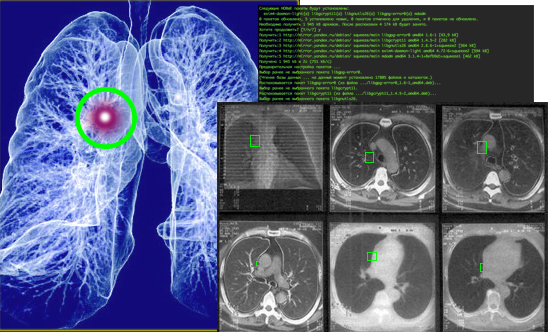

Кратко идея состоит в том, чтобы натренировать нейронную сеть, объединяющую большой массив данных о различных КТ-проявлениях рака легкого, более тонко распознавать ранние признаки этого заболевания на основе анализа низкодозных томографических срезов. При этом, каков процент выявления сейчас25.01.17